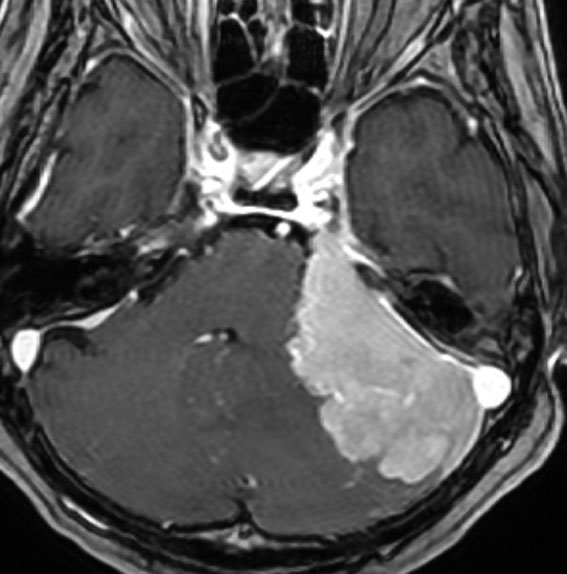

angiomatous meningioma WHO grade 1 血管腫様髄膜腫

術前検査ではまるで膠芽腫のような画像です。でも,開けてみれば髄膜腫ということはすぐにわかる肉眼所見です。硬膜の至る所から腫瘍血管が流入して出血性腫瘍です。